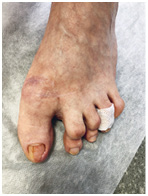

Девушка пыталась самостоятельно избавиться от мозоли с помощью мозольного пластыря с салициловой кислотой. Целостность кожного покрова была нарушена кислотами, входящими в состав пластыря. В рану попала инфекция и началось воспаление. Решали проблему с помощью хирурга.